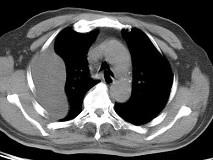

问题 男,28岁,胸闷一周,胸部CT如图,最可能的诊断为 ( )

选项 A、肺炎性假瘤 B、肺肉瘤 C、肺癌 D、包裹性积液 E、间皮瘤

答案 D